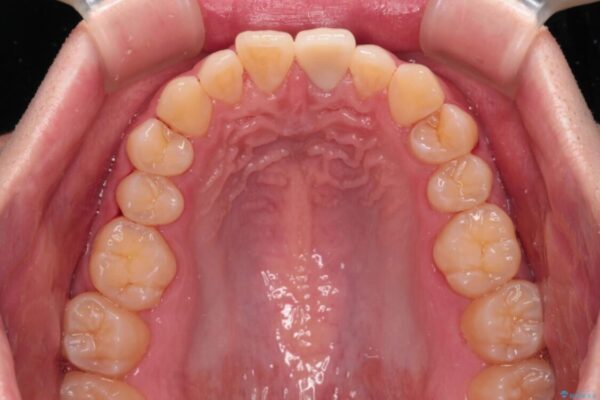

神経を取り除いたことで変色した前歯を気にして来院された患者様です。

神経を取り除いた歯は時間とともに変色してきます。

クリーニングやホワイトニングでは改善できないため、オールセラミッククラウンなどによる補綴治療が必要となります。

治療後

• 変色した前歯をオールセラミッククラウンに 治療後画像